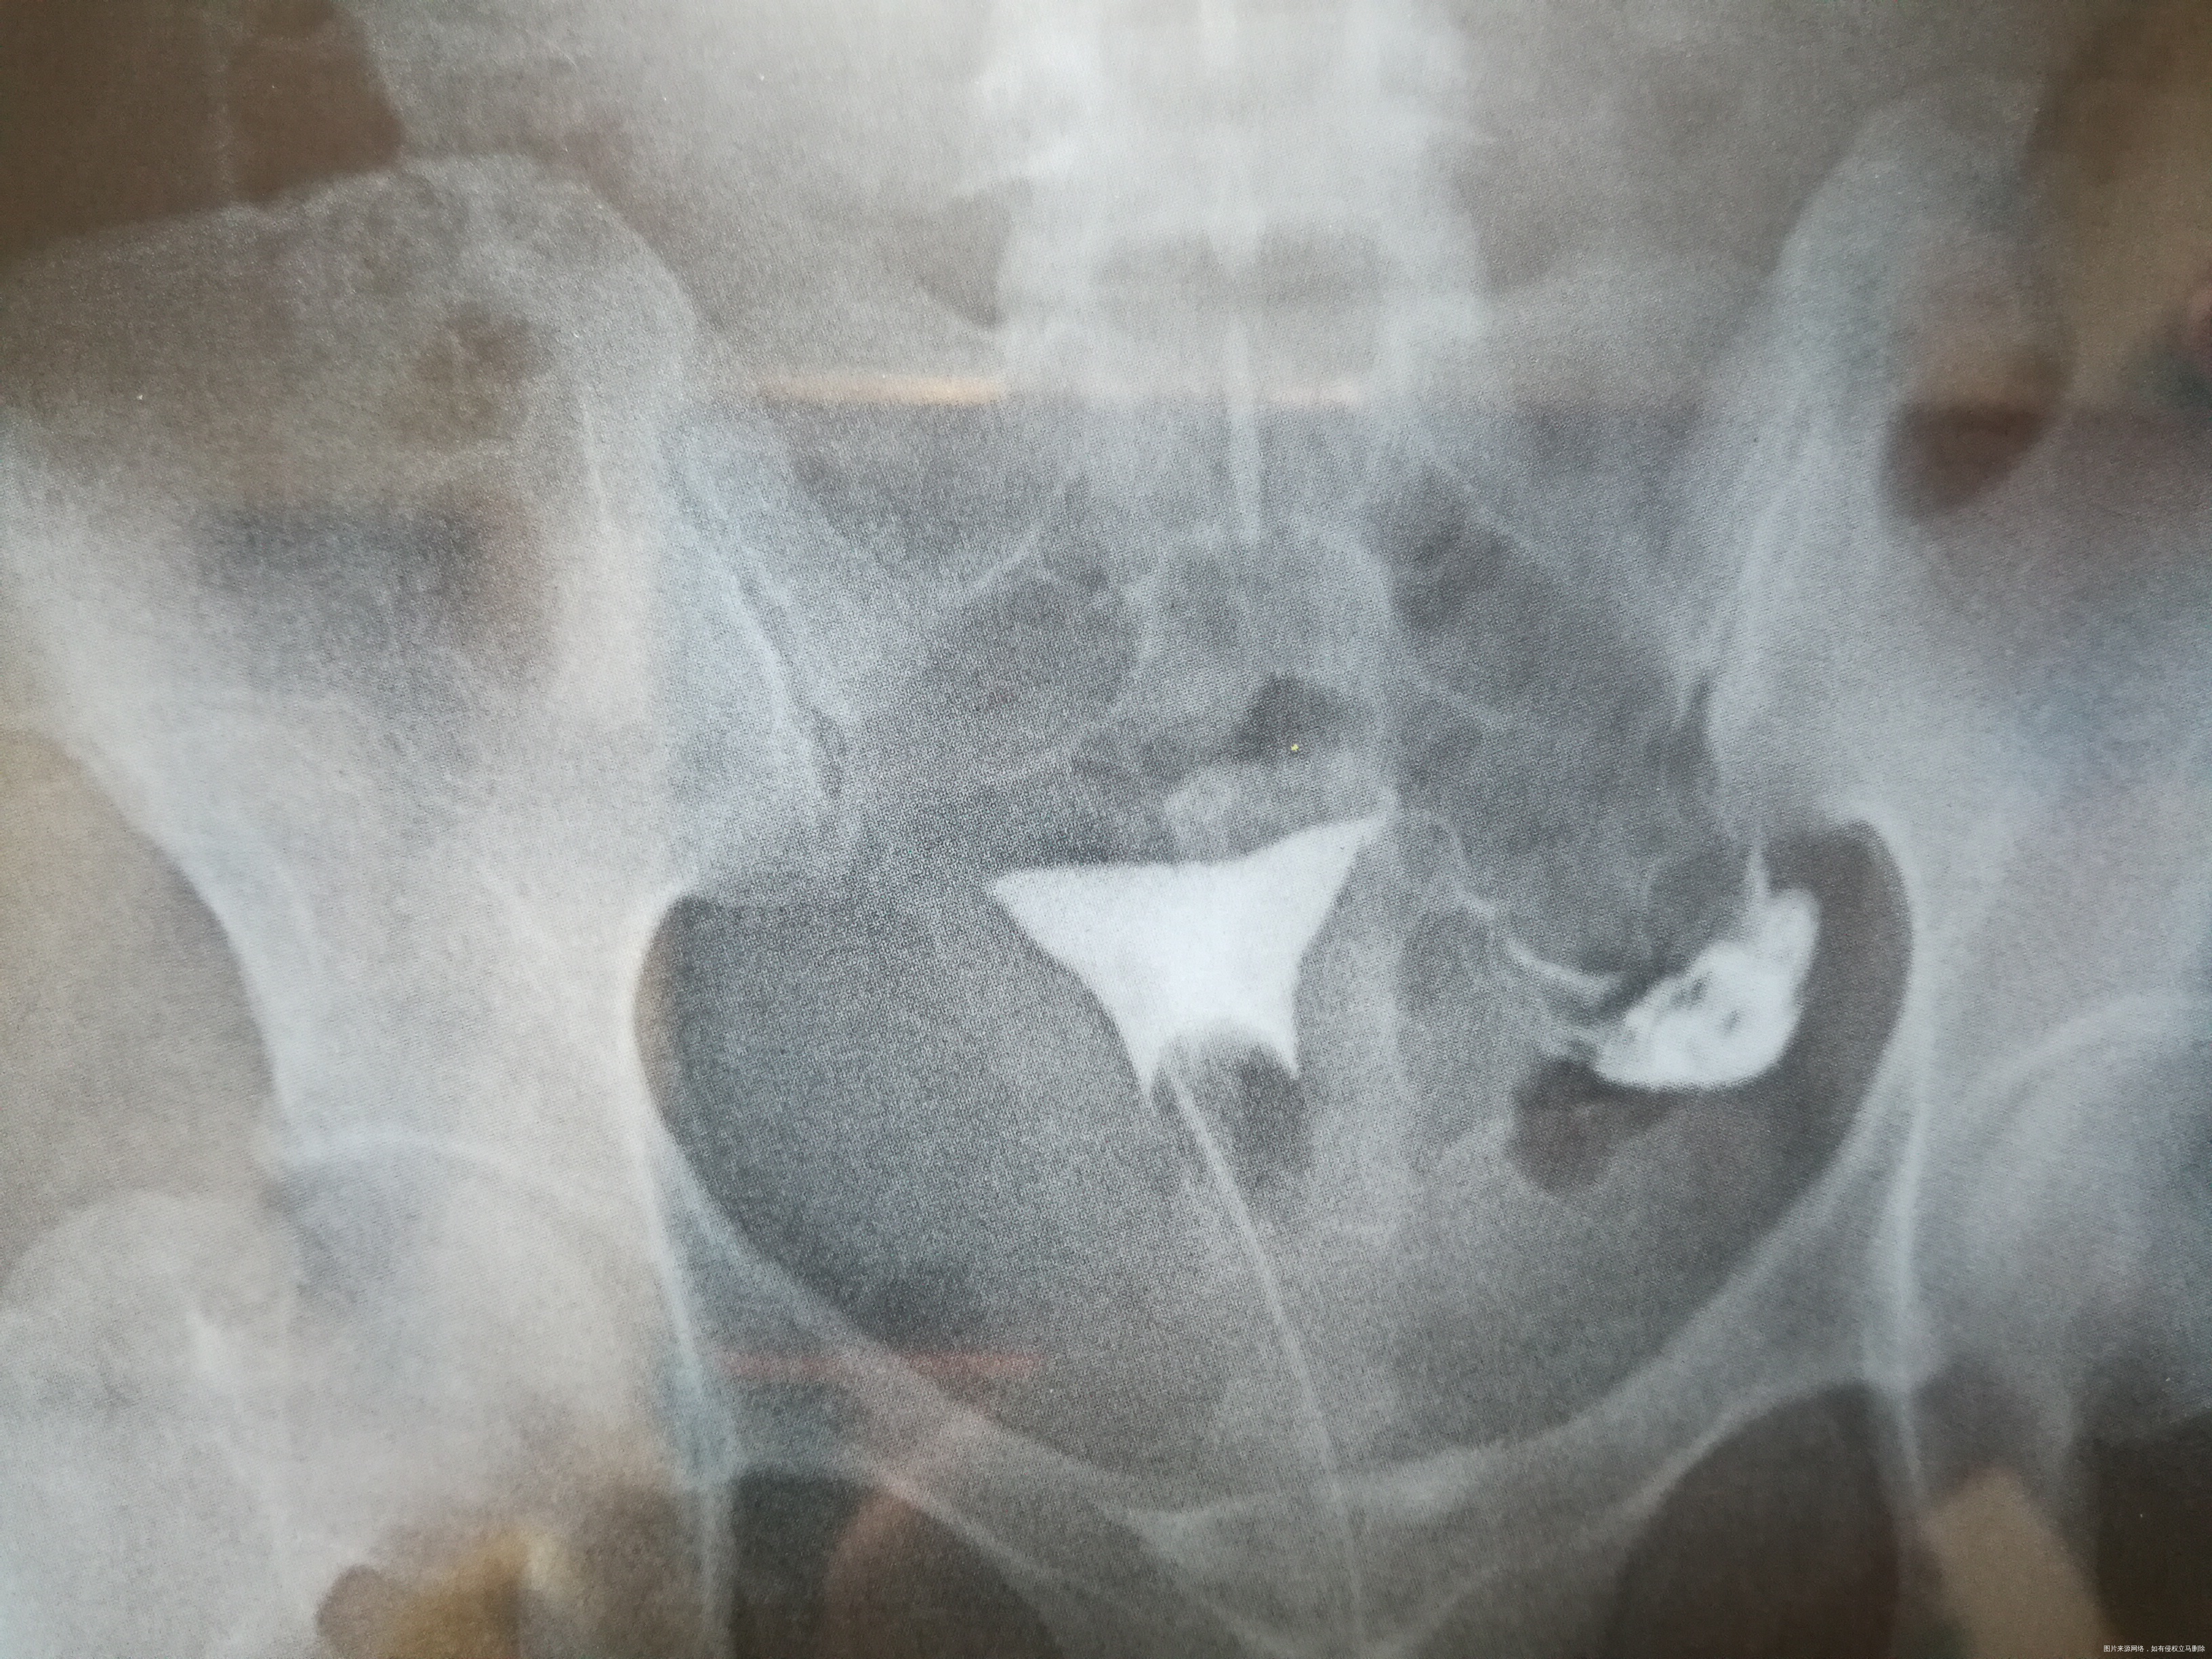

平片示盆腔区未见异常。电视下从双腔气囊管内注入30%碘普罗胺3ml、6ml分别点片示:子宫腔呈一倒立三角形位于耻骨联合上5.4cm正中线偏右侧0.8cm处,大小约4.0cm×3.6cm,宫腔显影均匀、边界清晰;左输卵管各段显影,边界清楚,未见闭塞、积水征;右侧输卵管从间质部起未见显示。30分钟后复查见大部分造影剂流入盆腔弥散,余无特殊。

(3张造影图的时间分别是:14 51 44,14 53 48,14 54 26)

1、子宫腔、左输卵管未见明确异常。 2、右侧输卵管从间质起未见显示,请结合临床。